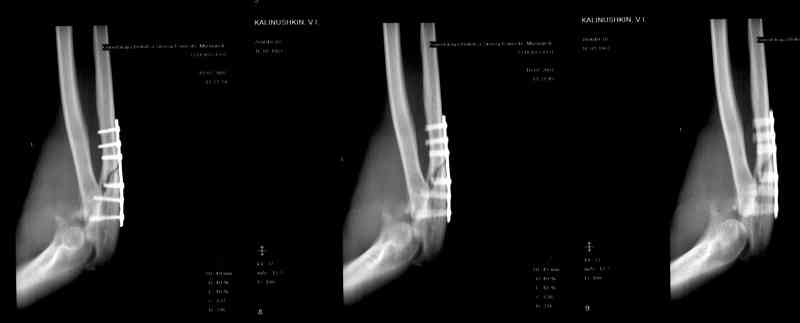

Больной был прооперирован.Протеза головки лучевой у нас нет. Решили с локтевой костью пока ничего не делать. Выполнили операцию по востановлению связочного аппарата локтевого сустава(см.схему)- модфикация метода W.E.Spring,сухожилие мы фикстровали к винту на локтевой.

Естественно ревизия сустава и удаление рубцово-хрящевидных тканей.Затем наложили аппарат Илизарова с шарнирами. Первые 2 дня сустав был фиксирован трансартикулярно 2-мя спицами, затем спицы удалили. И больной начинает движения в аппарате.

Прилагаюся послеоперационные рентгенограммы.

Планиуем аппарат на 3-4 нед.

Что-то по снимкам ось шарниров с осью вращения локтевого сустава не сильно близко.